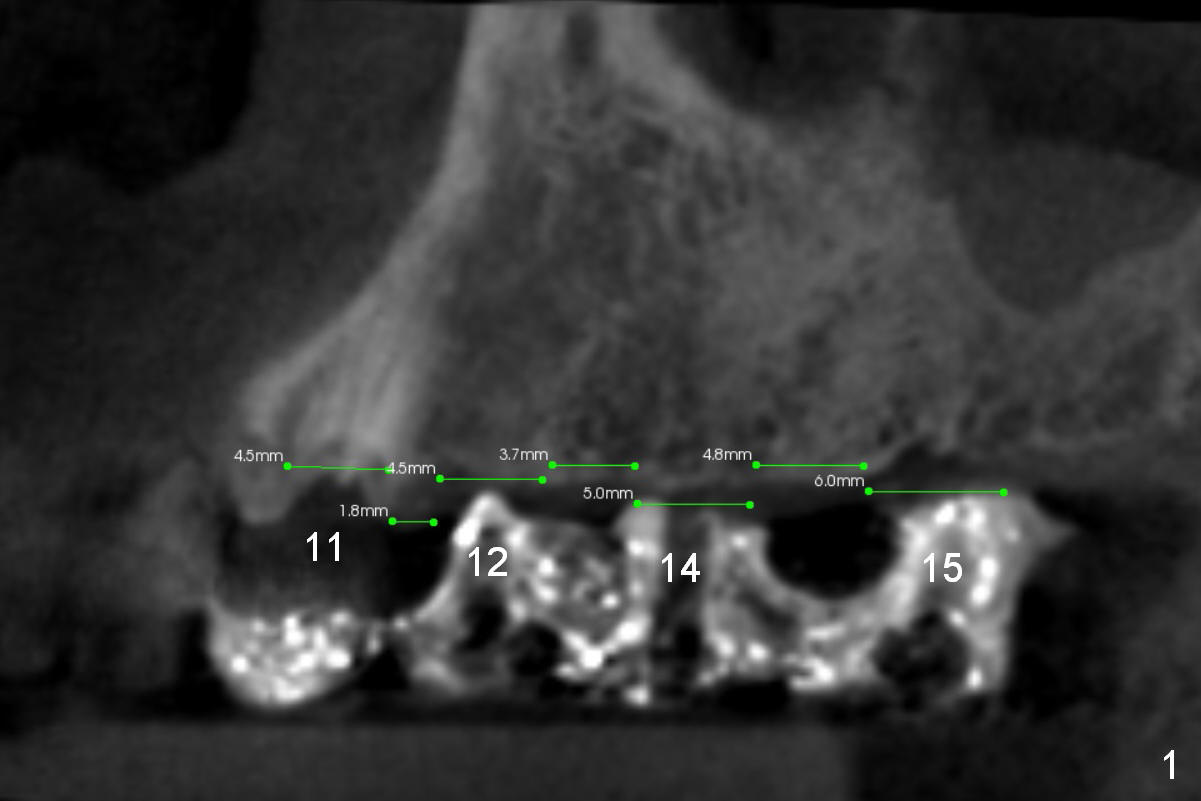

Implant Placement in Upper Left Sextant

Because of cross bite, there will be one less implant to be placed in the upper left sextant (Fig.1). Maintain certain distance between implants. After extraction of #11 and socket treatment with Clindamycin, start osteotomy at 17 mm and insert a parallel pin (Fig.2). Use surgical stent to start osteotomy through the gingiva at #12,14 and 15. Make incision and adjust the position of the osteotomies at #12,14,15. The depth will be 14, 14 and 9 mm, respectively. Insert parallel pins and take 1st intraop PA. Extend the osteotomies to their final depth in accordance with the design (Fig.2-5).